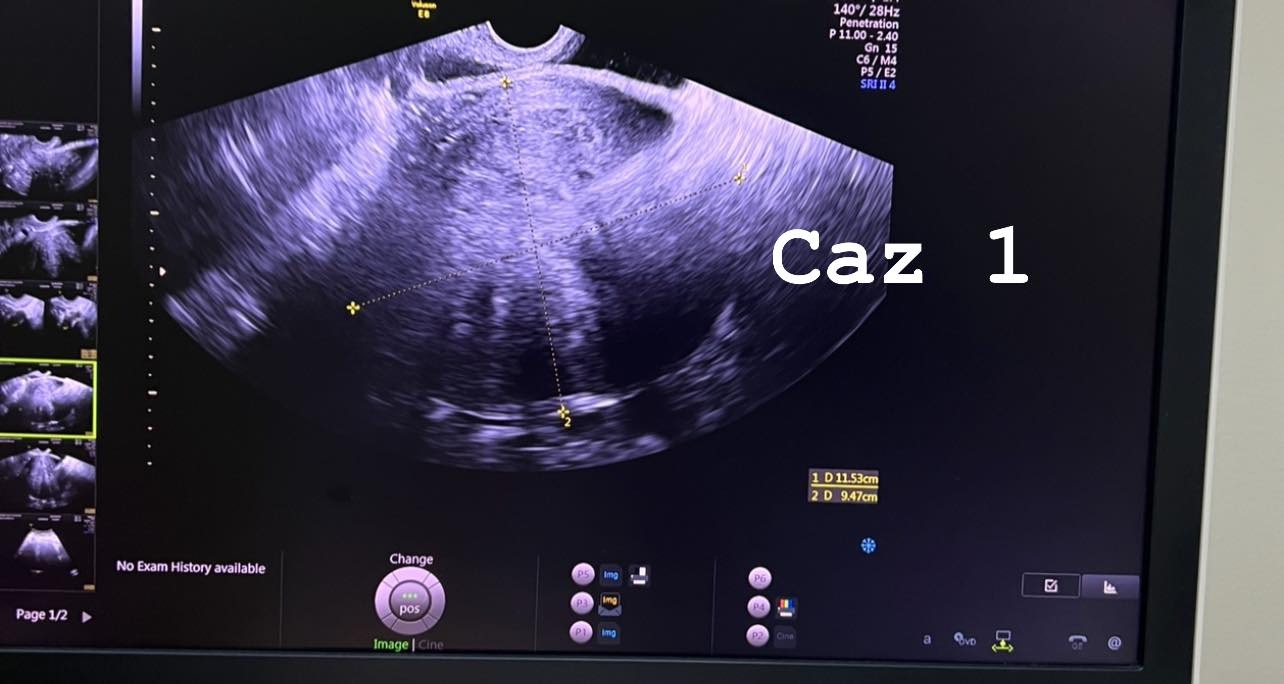

O doctoriță din județul Botoșani a transmis un avertisment pentru femeile cu vârsta peste 40 de ani, care acuză simptome precum: balonarea, dureri de burtă. Alexandra Ciobanu arată că, într-o singură zi, trei femei care au peste 45 de ani au ajuns la ea cu fribrom uterin și chist ovarian.

„Toate sunt paciente peste 40 ani si toate 3 nu se plângeau de nimic ieșit din comun, desi semnale de alarma existau…Se întâmpla adeseori ca pacientele sa nu acorde importantă unor simptome, considerând ca este firesc sa doara burta uneori, este firesc sa fie balonate, pun multe simptome pe seama consumului anumitor grupe alimentare, stresului, etc.